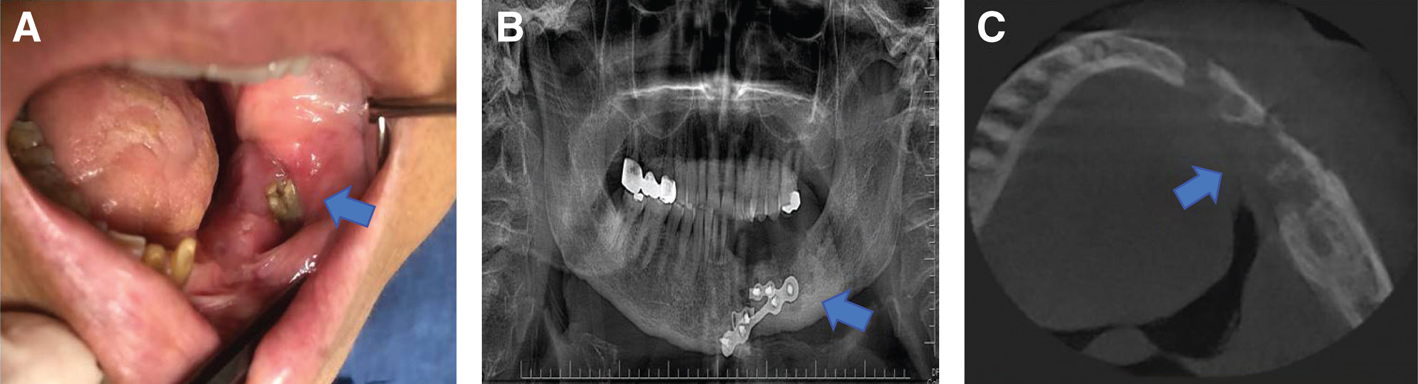

The ORNJ may manifest with a variety of signs and symptoms after RT or CCRT. Common ORNJ symptoms include facial deformity, discomfort, foul breath (halitosis), dysgeusia, dysesthesia or anesthesia, trismus, difficulties with mastication, deglutition, difficulty eating and speaking, intraoral or orocutaneous fistula formation, pathologic fracture, and localized or systemic infections (18) (Figure 1A-C). ORNJ severely worsens patients’ quality of life (QoL) after the oncologic therapy as a result of these serious symptoms and/or their consequences (19). Research on this topic is limited despite the fact that practically all studies demonstrate that ORNJ negatively affects health-related QoL (HRQoL) measurements (2023). The HRQoL assessment gathers data on the psychosocial health of patients as well as the relevance of the specific disease state and its treatment. In light of this, HRQoL-based studies are growing in popularity as useful methods for evaluating functional and psychosocial outcomes in conjunction with relapse and survival rates in a variety of disorders (24).

Fig 1

Figure 1. Osteoradionecrosis of the lower jaw in the left retromolar region (blue arrow). A: clinical intra-oral view. B: panoramic radiograph image. C: axial cone-beam computed tomography image.